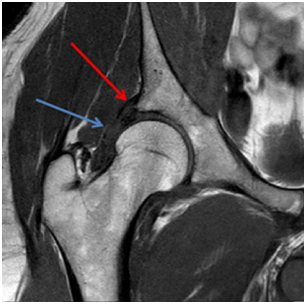

MRI shows injury of the superolateral aspect of the acetabular labrum, acetabular, femoral head and neck edema, joint effusion and partial tear of the iliofemoral ligament (Figures 1-3).

Figure 3 MRI in T2 SPIR sequence in the axial section demonstrating femoral neck edema (blue arrow) and partial rupture of the iliofemoral ligament (red arrow).